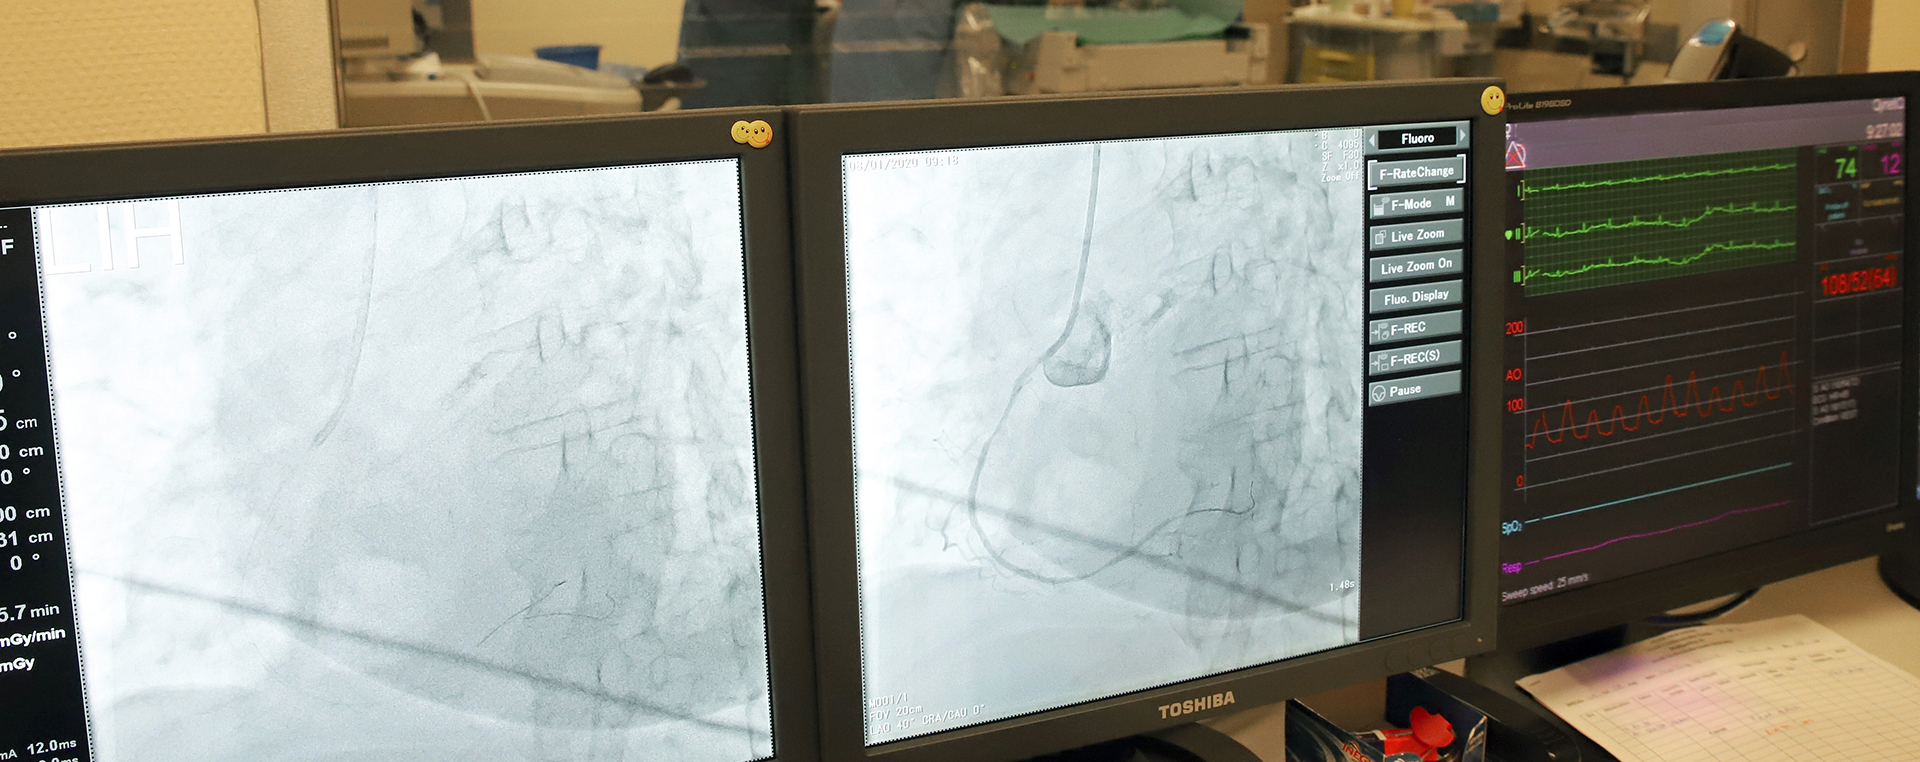

• Az Uzsoki Cardiovascular Center Kft. (UCC) által üzemeltetett Intervenciós Hemodinamikai Labor 2016. április 1-én kezdte meg a működését és a kardiológiai betegellátást. A kimagasló szakmai team jelenlétét igazolja az, hogy az intervenció legkomplexebb ágához is értő, strukturális beavatkozásokban is jártas orvosok dolgoznak nálunk.

• Orvosainknak olyan eszközökre is van nemzetközi licence-e, amelyek egyedül állóak hazánkban.